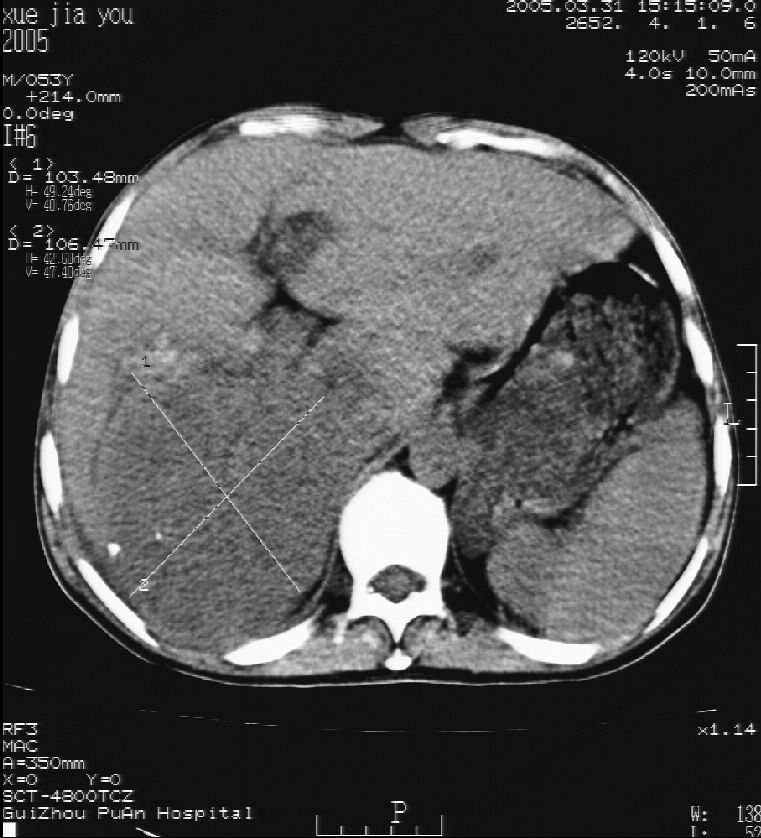

男 55岁  反复上腹痛1年,伴恶心呕吐。2005年做第一次检查后,到外院做b超检查提示肝囊肿,未做任何手术。2006年做过胆总管结石术。骨窗未见异常

这个病灶很有意思,怎么可能没有了呢?我考虑当时很可能是肝脏脓肿(b超示囊肿是有可能误诊的,因为影像表现都是低回声吗?),现在脓肿吸收了,肝脏萎缩,肝裂增宽了.别的肝叶代偿增大,不过现在左内叶的确有个占位,肝内多发结石,脾脏比以前大,不排除有肝硬化可能.建议增强扫描给于定性!!!!

肝硬化\\脾大,肝左叶肝癌可能性大,建议增强扫描.肝内胆管多发性结石.

1, 肝硬化,脾大;2,肝左叶肝癌可能性大,建议增强扫描.3,肝内胆管多发性结石.

考虑肝内胆管多发结石引起的肝内局部炎症,这样可以解释2005年肝右叶病灶的吸收和左叶新病灶.

肝硬化、脾大、肝内胆管多发结石。肝左叶低密度占位。建议增强扫描.排除肝癌